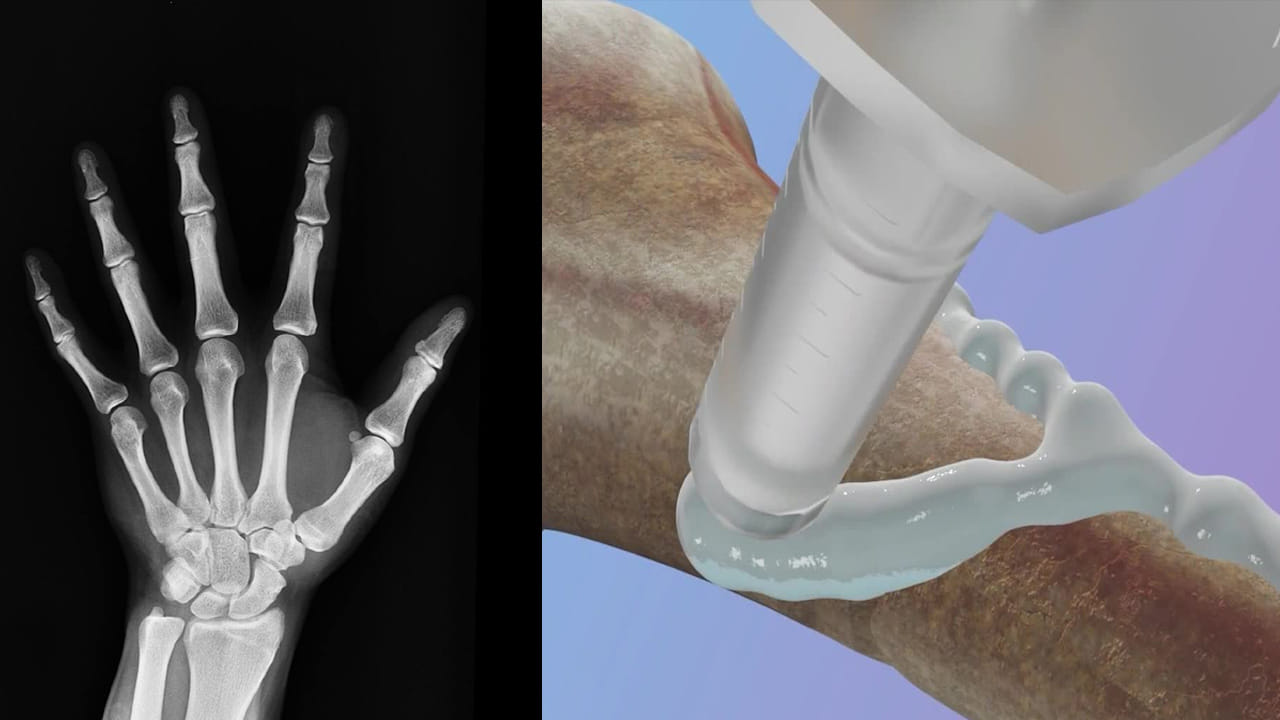

చైనా పరిశోధకులు.. సరికొత్త ఆవిష్కరణను ప్రపంచానికి పరిచయం చేశారు. పగుళ్లు, విరిగిన ఎముక ముక్కలను కేవలం మూడు నిమిషాల్లో చికిత్స చేయడానికి ఉపయోగపడే ఎముక జిగురు(Bone Glue) ను చైనా పరిశోధకులు అభివృద్ధి చేశారు. ఎముకల పగుళ్లను సరిచేయడానికి, అలాగే ఆర్థోపెడిక్ పరికరాలను అతికించడానికి.. ఇది కీలకం కానుంది.

“బోన్ 02” బోన్ గ్లూ అని పిలువబడే ఈ ఉత్పత్తిని తూర్పు చైనాలోని జెజియాంగ్ ప్రావిన్స్లో బుధవారం (సెప్టెంబర్ 10) ఒక పరిశోధనా బృందం ఆవిష్కరించిందని గ్లోబల్ టైమ్స్ తెలిపింది. సర్ రన్ రన్ షా హాస్పిటల్లో ఈ పరిశోధనకు నాయకత్వం వహించిన అసోసియేట్ చీఫ్ ఆర్థోపెడిక్ సర్జన్ లిన్ జియాన్ఫెంగ్ మాట్లాడుతూ.. నీటి అడుగున వంతెనకు గట్టిగా అతుక్కుని ఉన్న గుల్లలను గమనించిన తర్వాత.. ఎముక జిగురును అభివృద్ధి చేయడానికి ప్రేరణ పొందానని పేర్కొన్నారు.

మిస్టర్ లిన్ ప్రకారం.. రక్తం అధికంగా ఉండే వాతావరణంలో కూడా, ఈ అంటుకునే పదార్థం రెండు నుండి మూడు నిమిషాల్లోనే ఖచ్చితమైన స్థిరీకరణను సాధించగలదు. ఎముక నయం అయినప్పుడు ఈ జిగురు శరీరం సహజంగా గ్రహించగలదు.. ఇంప్లాంట్లను తొలగించడానికి మరొక శస్త్రచికిత్స అవసరం లేకుండా చేస్తుంది.

“బోన్-02” భద్రత – ప్రభావ ప్రమాణాలు రెండింటిలోనూ మంచి పనితీరును ప్రదర్శించిందని ప్రయోగశాల పరీక్షలు నిర్ధారించాయి. ఒక ట్రయల్లో, ఈ ప్రక్రియ 180 సెకన్లు లేదా మూడు నిమిషాల కంటే తక్కువ సమయంలో పూర్తయింది.. అయితే సాంప్రదాయ చికిత్సా పద్ధతులకు స్టీల్ ప్లేట్లు, స్క్రూలను అమర్చడానికి పెద్ద కోత అవసరం. CCTV ప్రకారం , 150 మందికి పైగా రోగులలో ఎముక జిగురును విజయవంతంగా పరీక్షించారు..

అతుక్కొని ఉన్న ఎముకలు గరిష్టంగా 400 పౌండ్లకు పైగా బంధన శక్తిని, దాదాపు 0.5 MPa కోత బలాన్ని, దాదాపు 10 MPa సంపీడన బలాన్ని చూపించాయి.. ఇది ఉత్పత్తి సాంప్రదాయ మెటల్ ఇంప్లాంట్లను భర్తీ చేయగల సామర్థ్యాన్ని కలిగి ఉండవచ్చని హైలైట్ చేస్తుంది. ఇది ప్రతిచర్య, సంక్రమణ ప్రమాదాలను కూడా తగ్గించగలదని శాస్త్రవేత్తలు పేర్కొన్నారు.